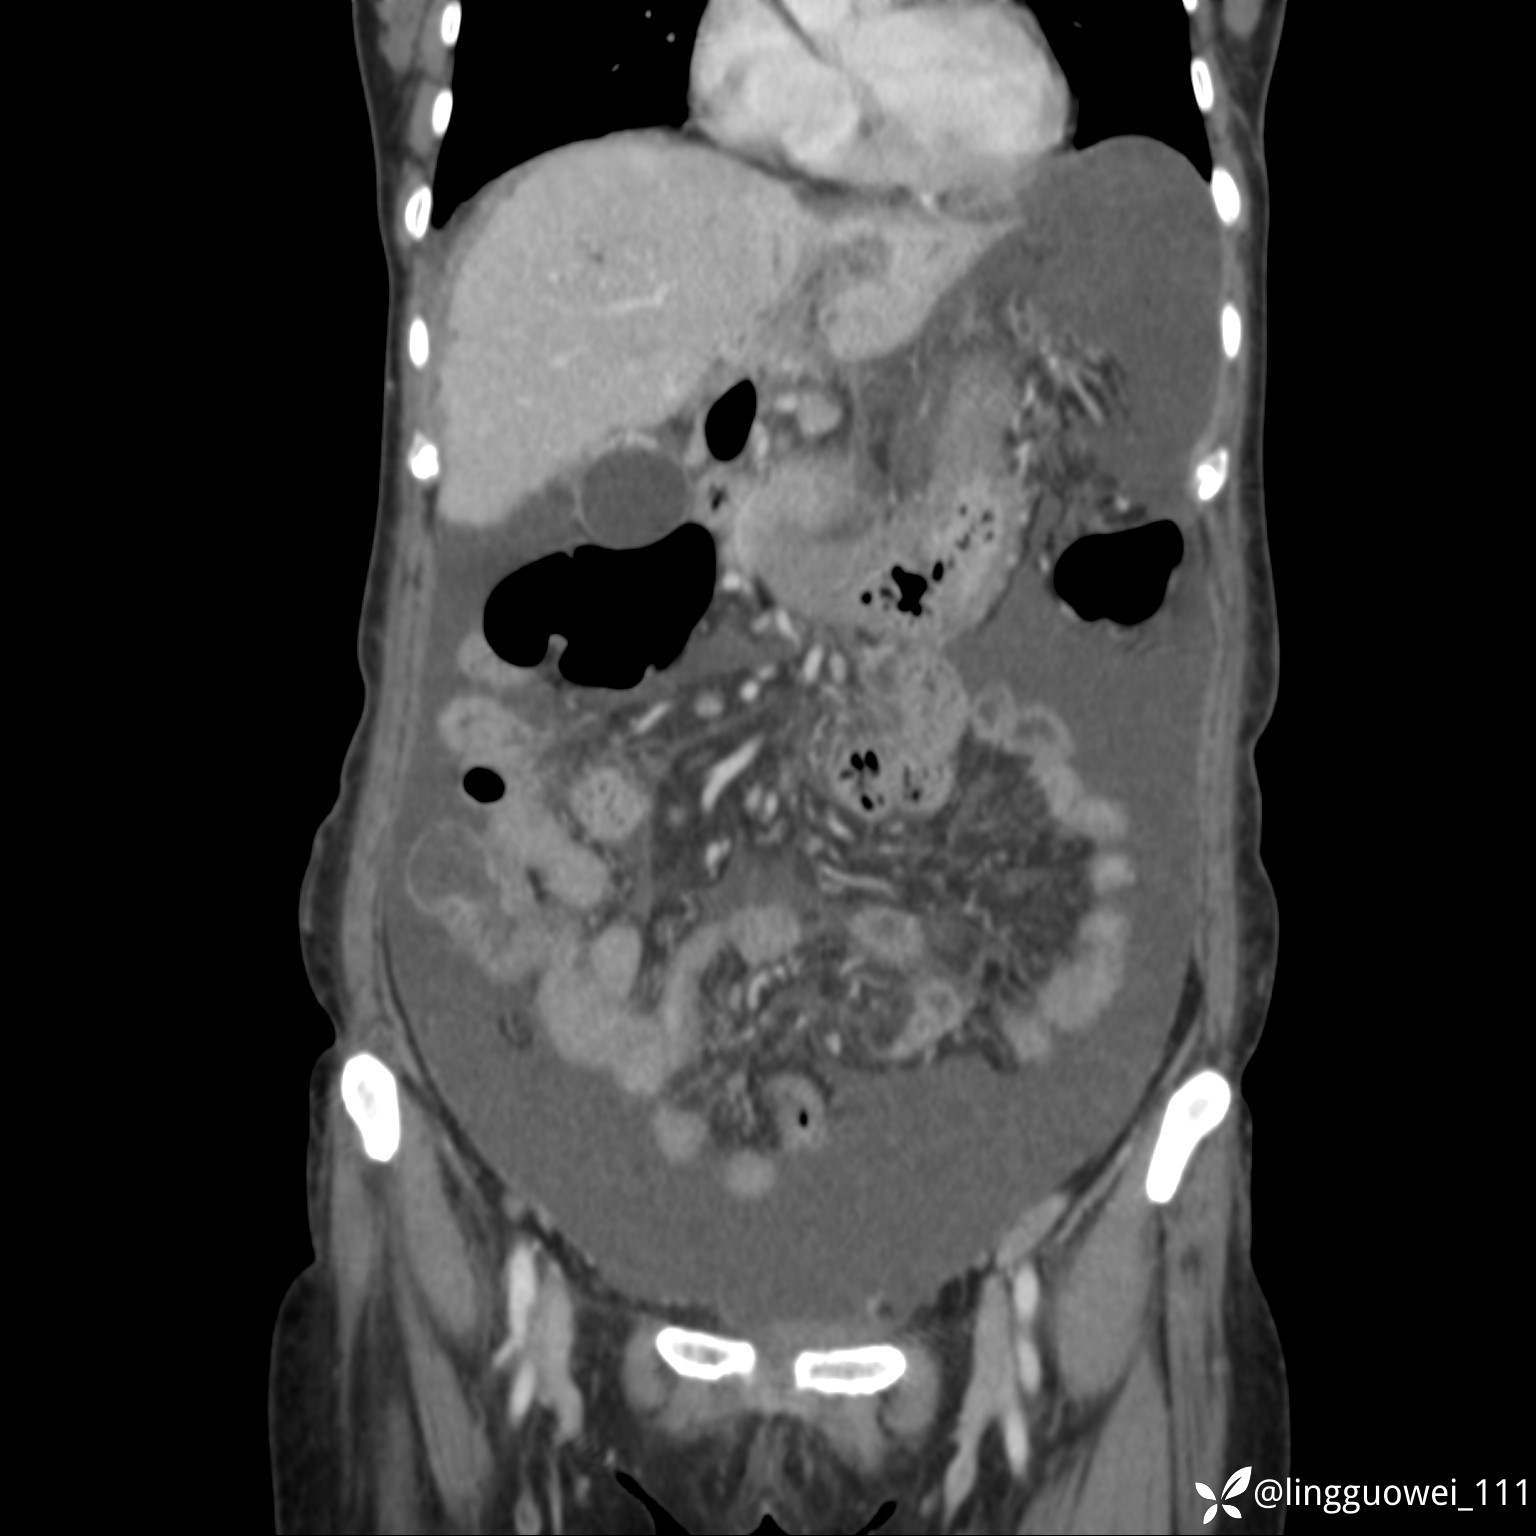

病例女,65岁,门诊行胃肠镜检查后,说腹胀入院检查,CT能发现病因吗?已公布结果

主诉:门诊行胃肠镜检查后,诉腹胀,入院检查,肝有病变吗?腹膜及腹腔的表现有特征性吗?

门脉期: